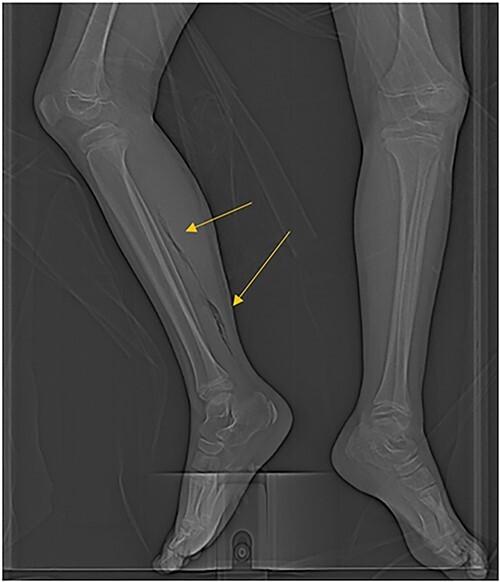

A distinct case of an 8-year-old female with cyclic neutropenia presenting with abdominal sepsis and myonecrosis requiring a bowel resection and leg fasciotomy.

is a very rare cause of severe spontaneous pediatric enterocolitis and is often associated with underlying malignancy or immunocompromise. Likewise, cyclic neutropenia is a rare congenital immunodeficiency that is characterized by cyclical periods of neutropenia, often with more severe symptoms in the pediatric population. Here, we present a unique case of spontaneous enterocolitis, sepsis, and myonecrosis in a child with undiagnosed cyclic neutropenia. Early recognition of pediatric sepsis, frequent reevaluation and identification of rapidly progressive infection, and early surgical intervention are critical for the effective management of a rare and severe infection.